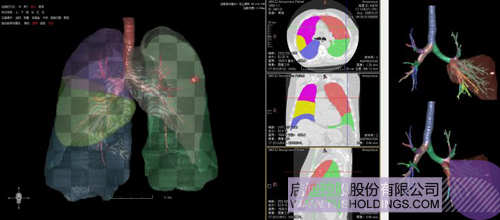

數(shù)字肺——肺結(jié)節(jié)手術(shù)規(guī)劃系統(tǒng)

完整的三維影像智能分析技術(shù);

完整的三維可視化以及相關(guān)建模、幾何分析技術(shù);

肺動脈栓塞輔助診斷